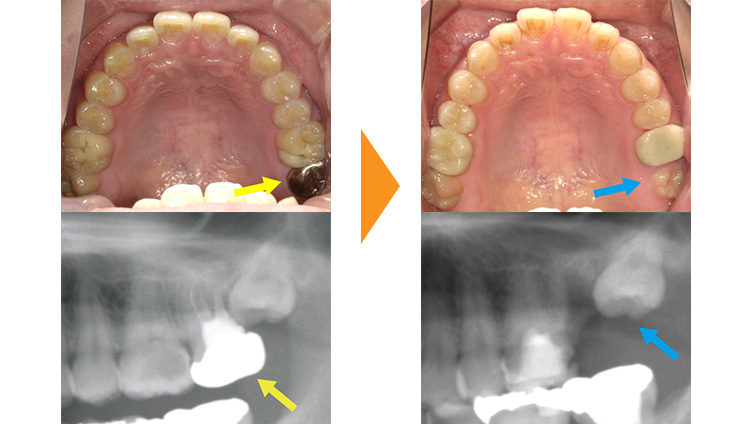

紹介元の歯医者さんで奥歯を抜歯しないといけないと言われた患者様です。予後不良の左上7を抜歯後、部分矯正にて左上8の牽引・排列を行った例となります。

左上7の状態が悪く抜歯適応です。(黄矢印)

左上7抜歯後、左上8が自然に生えてくるのを待ちました。(青矢印)

リンガルアーチとワイヤーを使用し、約9か月で排列しました。

矯正後、仮歯の修正をしていただき治療は終了となります。(赤矢印)

この方のように全体的な歯並びに問題はないものの、むし歯が原因で抜歯になってしまった場合に部分的な矯正治療が効果的な場合があります。

矯正治療にて本来であれば使えなかった親知らずを使用し、インプラントや入れ歯を回避することができました。